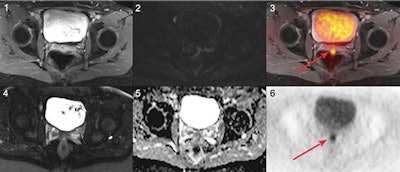

PET/MRI can better detect and classify local lesions and distant metastases in women suspected of having recurrent pelvic cancer than MRI alone, according to a study presented at the recent RSNA 2017 annual meeting.

Based on the reference standard, 55 patients (77%) experienced a cancer recurrence, while 16 patients (23%) had no such recurrence. PET/MRI correctly identified all 55 patients (100%) with cancer recurrence compared with MRI alone, which correctly identified 46 patients (83%) with cancer recurrence (p < 0.01). In addition, PET/MRI and MRI alone both correctly identified 15 (94%) of the 16 patients with no cancer recurrence.

In the lesion-based analysis, the reference standard identified 181 (75%) malignant lesions and 60 (25%) benign lesions. PET/MRI identified all malignant lesions, MRI alone discovered on 75%. As for the correct identification of benign lesions, PET/MRI (97%) and MRI were much more comparable (93%).

While PET/MRI correctly identified all malignant lesions, the hybrid modality misclassified two foci of infection as malignant lesions. By comparison, MRI's missed 34 malignant lesions, which included 32 FDG-positive nonenlarged lymph node metastases. MRI alone also misinterpreted 12 malignant lesions as benign, which included four local recurrences and three peritoneal metastases.

Among the patients with recurrence in the pelvic cavity, PET/MRI identified all 15 patients (100%) compared with MRI alone, which correctly identified only 11 patients (73%) in this category. Among patients with distant metastases, PET/MRI correctly identified all 40 patients (100%), compared with 32 correctly identified patients (80%) by MRI alone.